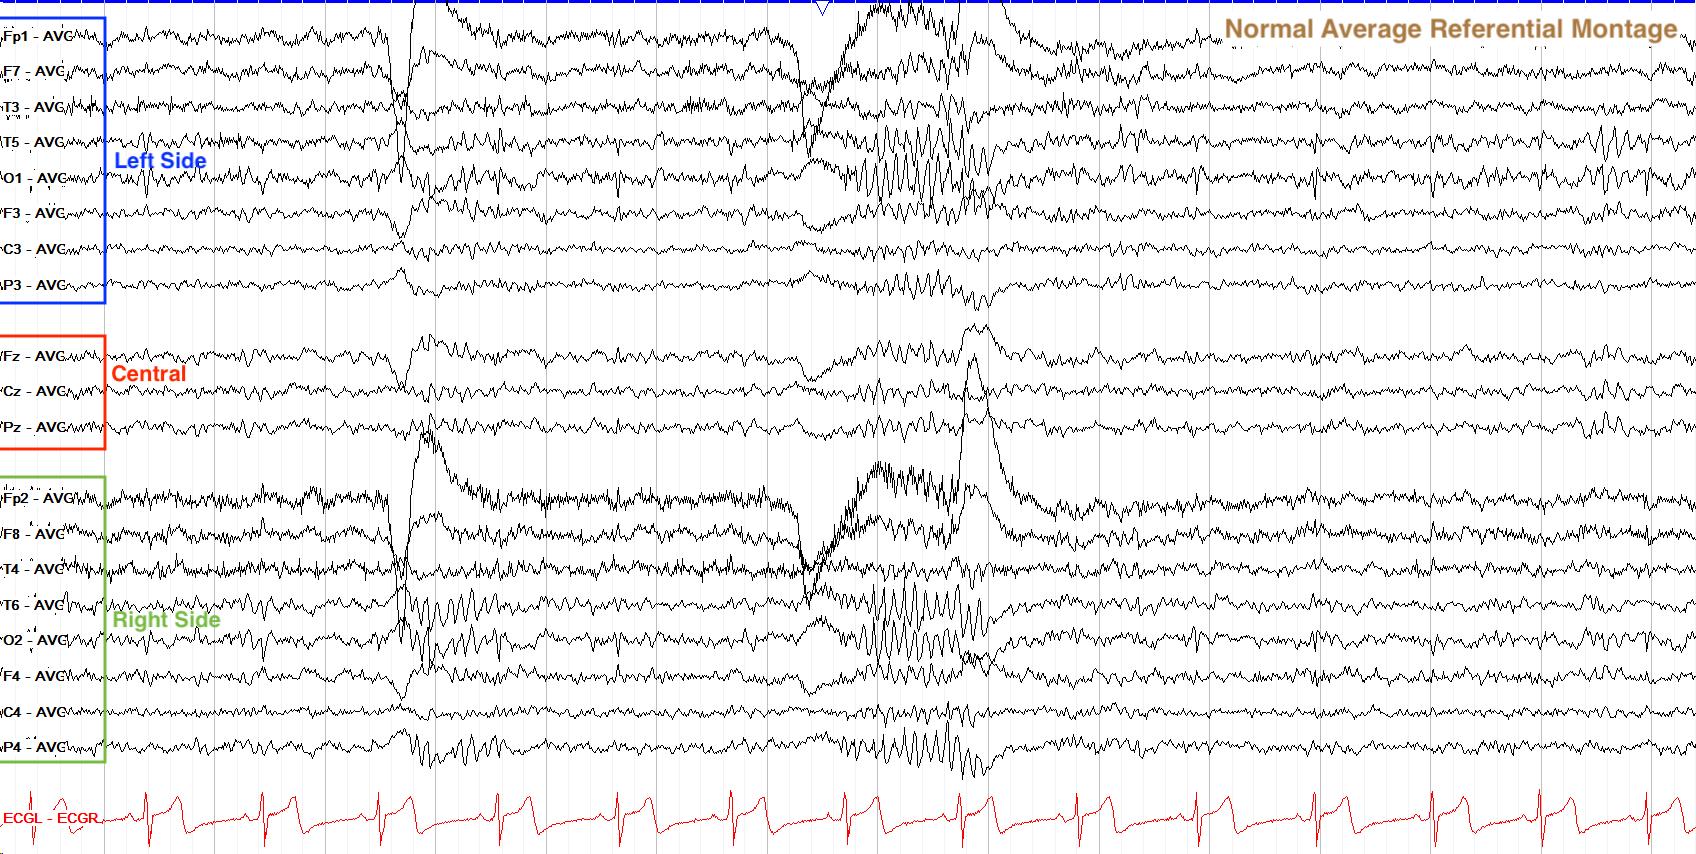

枚举出计算机的所有可记录计算维度,从医⽣当前的读图分析⾏为进上右图归纳: 1. 读图分析的基本维度:时⻓、频率、波幅、位置是记录的基本维度,是对客观世界的物理描述;使 ⽤电流作分析的,故接下来不着重论述; 2. 抽象计算的维度:调频、调幅、频带、功率、能量也是 种物理描述,在⼈的视⻆下经历过简单的 计算,故单独归纳,并简要说明其位置信息 说明 调频 脑波频率变化的范围,反应脑电活动的规律性 调幅 脑波波幅变化的规律,反应脑电活动的稳定性 频带 ⼤脑不同的活动状态的体现 功率/能量 活动强度的体现,不同的计算⽅式对结果会有影响,然⽽强度通常以颜⾊去展 现,在⽤⼾读图的过程中并不会对数值精确的感受并不会那么⾼,系统中的波 形要么具有能量值,要么具有功率值,因为能量有限的信号功率为0,⽽功率有 限的信号能量为⽆穷⼤。 般来说,周期信号和随机信号是功率信号⽽⾮周期 的确定信号是能量信号 位向 活动的⽅向 3. 形态计量的维度:脑电波的成形⽅式塑造着⼈观察⽅式,通过波形是对基本维度的定性归纳,即基 本维度是波形的度量;由波形衍伸出的临床分析是主要分析的⽅法;在读图软件⾥,波形的调整参 数得关注:灵敏度、滤波、⾛纸速度、陷波;她们影响着波形的展⽰与识别,参数的⻓期固定塑造 着⽤⼾对图形的识别 说明 波形 形态计量在EEG检查中的发展:医⽣通过观察总结如下相关性,不同的波形会 在不同的⼤脑活动状态中出现,故可以通过波形进⾏状态的识别:纺锤波;棘 波;尖波;不同的波形会在特定癫痫或癫痫综合征中出现,故可以推测可能疾 病并结合其它检查综合论证 灵敏度 uv/mm,屏幕尺⼨下,每毫⽶映射的幅度值

⾛纸速度 s/mm,屏幕尺⼨下,每毫⽶映射的时间 陷波 50Hz的过滤 4. 波形 说明 导联组合 波幅是 种电势差(活动)的识别,导联组合是对不同点位电势差的描述,考 虑电极放置的稳定性,医⽣会选择较稳定的点位作为参考电位(如C3 C4,A1 A2)然⽽周围异常放电时会导致参考电极活化,则会替换导联编排⽅式,如采 取双极导联看图; 导联组合下 的波形识别 在导联组合下,先识别⾼波幅位置,再识别波形⾼低趋势,有助于判定异常放 电的位置或者伪影 导联编排 受限于屏幕,导联组合通常竖向排布,较好的排布会根据其导联组合的⽅式调 整顺序 • Fp1左 Fp2右 F3左 F4右,医⽣会按照这种左右左右的⽅式对应在实际⼤ 脑中的位置 • 双极纵联: • 左右分区: